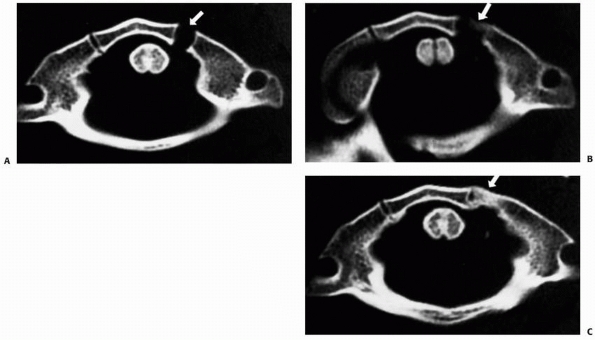

Plain radiographs often do not clearly show occipital condylar

fractures, and CT with multiplanar reconstruction usually is necessary

to establish the diagnosis.14,42 Tuli et al.225

recommended that a CT scan be obtained in the following circumstances:

presence of lower cranial nerve deficits, associated head injury or

basal skull fracture, or persistent neck pain despite normal

radiographs. Reports of associated cranial nerve deficits vary from 53%

to 31% of patients with occipital condylar fractures.9,92,225 Anderson and Montesano9 described three types of occipital condylar fractures (Table 18-2, Fig. 18-19):

type I, impaction fracture; type II, basilar skull fracture extending

into the condyle; and type III, avulsion fractures. An avulsion

fracture is the only type of occipital condylar fracture that is

unstable. Type I injuries are the result of axial compression with a

component of ipsilateral flexion. Type II injuries are basilar skull

fractures that extend to involve the occipital condyle and usually are

caused by a direct blow. Type III injuries are avulsion fractures of

the inferomedial portion of the condyle that is attached to the alar

ligament. Types I and II occipital condylar fractures usually are

stable and can be treated with a cervical orthosis. Type III or

avulsion fractures can be unstable and may require halo immobilization

or occipitocervical arthrodesis.6

![]() |

|

FIGURE 18-19 Classification of occipital condylar fractures according to Anderson and Monsanto.9 A. Type I fractures can occur with axial loading. B. Type II fractures are extensions of basilar cranial fractures. C.

Type III fractures can result from an avulsion of the condyle during rotation, lateral bending, or a combination of mechanisms. (From Hadley MN. Occipital condyle fractures. Neurosurgery 2002;50[Suppl]:S114-S119, with permission.) |